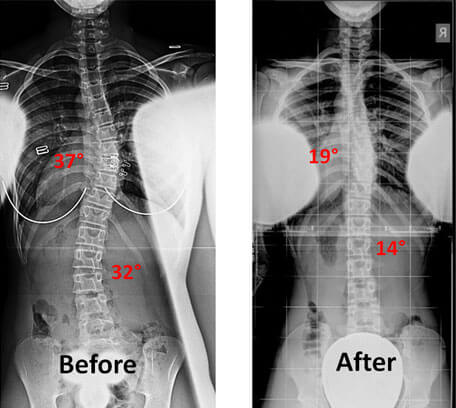

Spine Before & After SPS exercise

Before

After

Yes, SPS is used for both children and adults and has shown significant effectiveness in treating conditions common in adolescents. For example, in cases of adolescent idiopathic scoliosis (AIS), treatment with SPS has been shown to help a high percentage of patients avoid surgery.